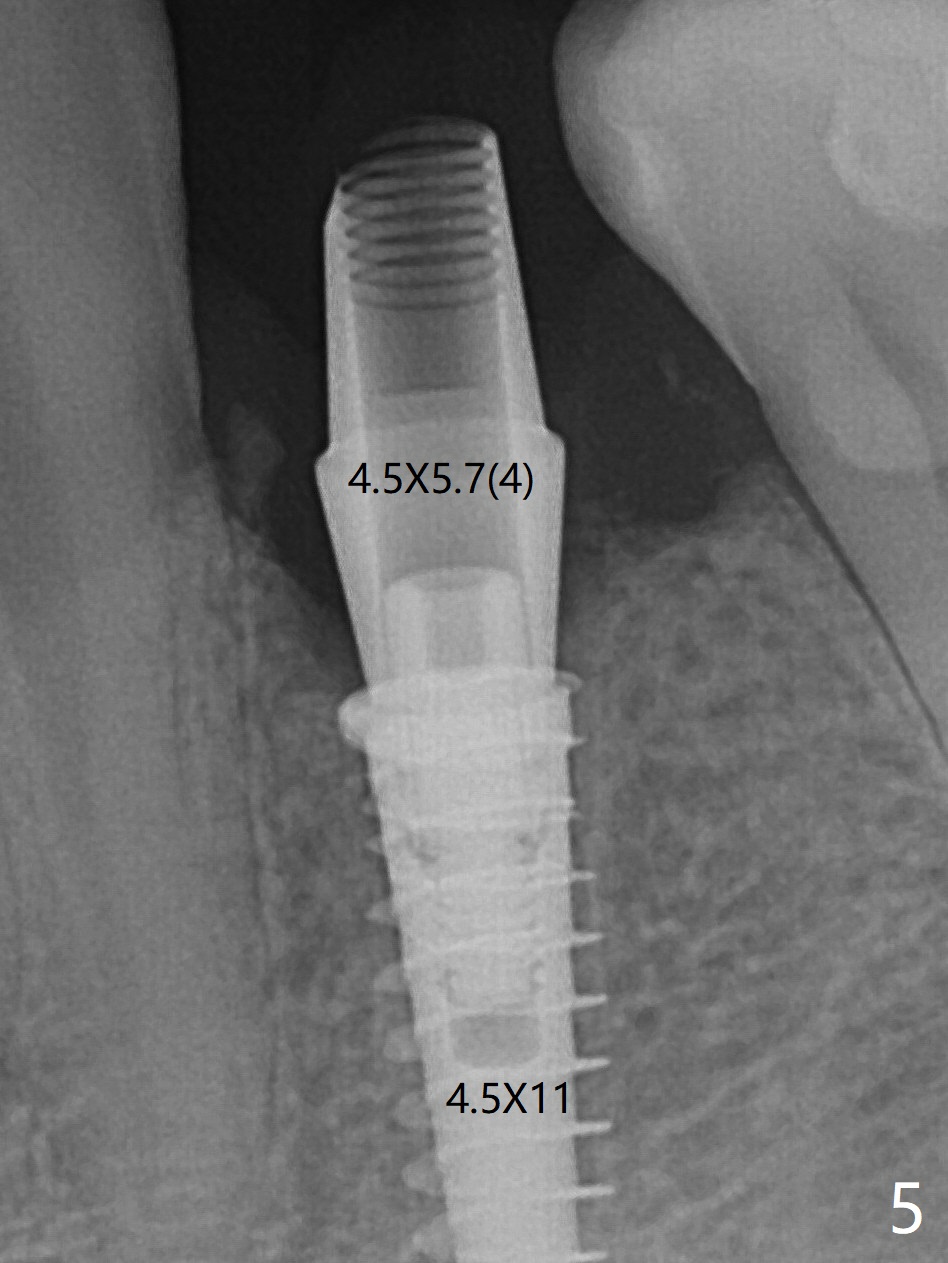

Three months post guide fabrication (coronavirus outbreak), the patient with loose post/crown returns for #21 extraction and immediate implant with guide (Fig.1 (*: post space)). In fact the root stump is flattened with diamond bur and 9 mm bone trimmer with guide before point drill. When the osteotomy finishes with 3.5x13 mm drill (under drilling with 10.5 mm offset), it has deviated buccal (Fig.2, 3,4); the outline of the bone trimmer mark is labeled by arrowheads in Fig.2. It appears that the center of the bone trimmer is dictated by that of the post space, as compared to Fig.1 *). When the root is removed except buccal shield (assuming that the deviation was due to the uneven surface of the root stump), the osteotomy is redone with guide, but remains buccal. Finally with buccal shield removal, a new lingual osteotomy is created free hand for a 4.5x11 mm implant (Fig.5) with 2-3 mm buccal gap for bone graft (Fig.6 * (literally)). In brief, bone trimmer also deviates according to resistance, basically irrelevant to the guide sleeve. The immediate provisional is intentionally removed 5 days postop to check whether a piece of gauze is retained in the socket as a gingival retraction cord for temporary crown fabrication; the buccal gap is kept with bone graft (Fig.7 *). No foreign body is in place. The margin of the abutment seems quite subgingival (Fig.8 *), but re-trimmed and polished provisional looks harmonious with the surrounding gingiva and the opposing dentition (Fig.9,10). The patient returns for prophy 2 months postop; the immediate provisional is removed for trimming and polishing. The bone graft seems to be integrated into a part of the gingiva (Fig.11 >). The abutment cuff appears to be too short.